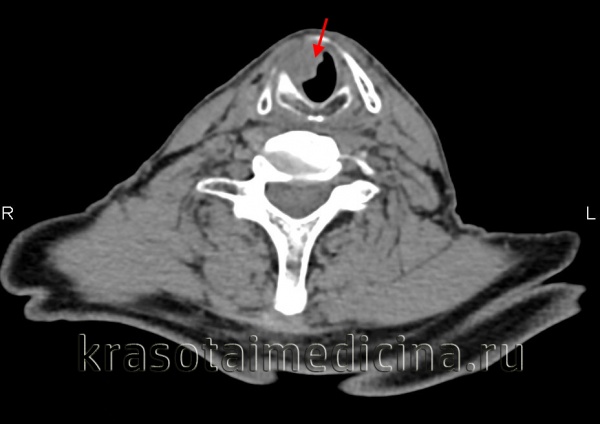

- Компьютерная томография (КТ) дает возможность определить размеры опухоли и ее распространение по лимфатическим узлам и окружающим тканям;

При постановке диагноза учитывают результаты КТ и МРТ гортаноглотки и УЗИ шеи. Решающую роль в выявлении рака гортаноглотки играют данные фиброфаринголарингоскопии. При проведении исследования специалист осуществляет визуальную оценку размера, локализации и структуры новообразования, а затем выполняет биопсию подозрительного участка. Окончательный диагноз выставляют онкологи на основании гистологического исследования.